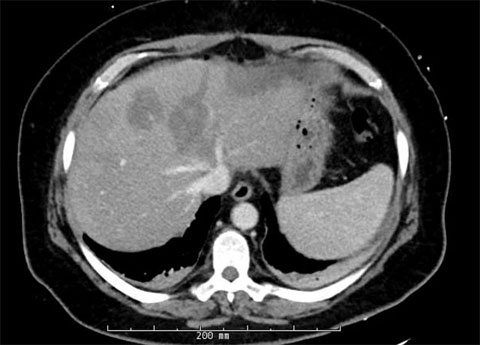

Post-second-surgery MRIs

Four weeks later, the patient came in for the second stage of the procedure, the right hepatectomy.

The patient had adequate growth in the liver remnant and was brought back for the removal of the right lobe of her liver where we removed approximately 70% of her liver, leaving 30% of it behind.